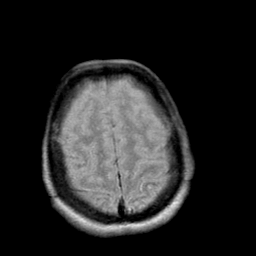

Creutzfeld-Jakob disease: proton density-weighted MR -- Slice #19

[Home][Help][Clinical] Slice 19